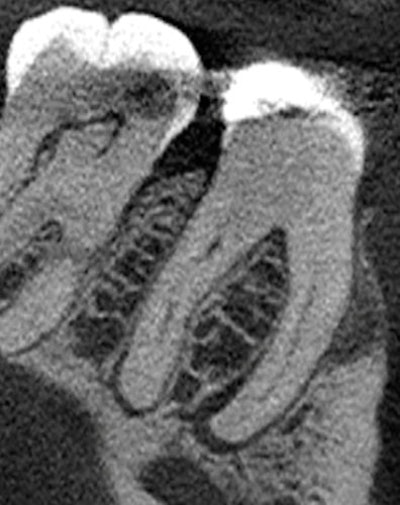

Figure 2: CBCT, axial view, tooth #30.

"Small hypodense lesions (radiolucent) are observed at the mesial and distal apices of tooth #30. The lesions are well defined and well corticated. There is no evidence of expansion in the coronal and axial projections for the small lesion at the distal apex. However, there is evidence of expansion (buccal) of the hypodense lesion located at the apex of the mesial root. Hyperdense bone is present at the periphery of the lesion, indicating a chronic inflammatory process."